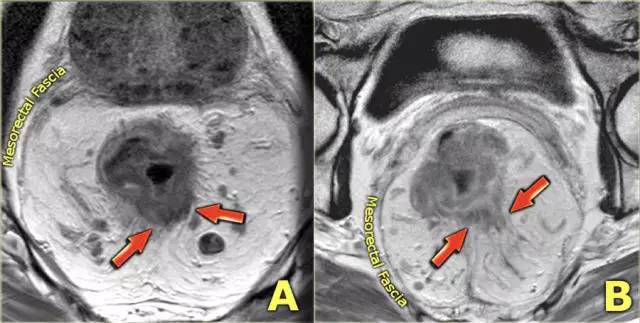

图 6 T3 直肠癌 MRF-,肿瘤浸润直肠系膜,1~4 点钟位置

图 7 直肠周围浸润(左);肿瘤局限于肠壁(右)

MRI 检测直肠周围组织浸润的敏感性为 82%,肿瘤侵犯或结缔组织增生反应均可表现为直肠周围浸润,为了避免分期不够,出现直肠周围浸润即作为 T3 期肿瘤。

T3 分期,累及 MRF

在 T3 肿瘤的描述中,报告应包括肿瘤边缘和 MRF 之间的最短距离。MRF 阳性导致局部复发的风险增加(当肿瘤边缘和 MRF 之间的距离小于 1 mm 时,MRF 被认为是阳性)。